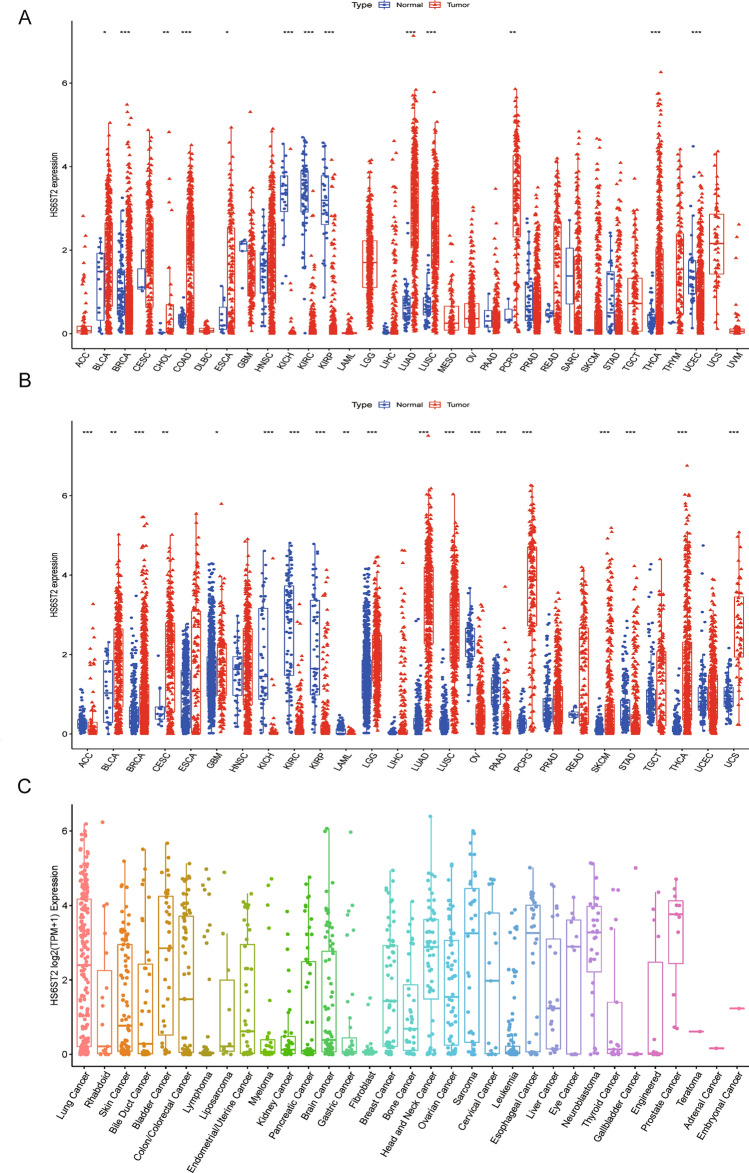

Differential expression of HS6ST2 between tumor and para-carcinoma tissues

We initially conducted a pan-cancer analysis of 33 malignancies from the TCGA database to have a deeper knowledge of HS6ST2 is expressed in different cancer types. Significant variations in HS6ST2 expression were detected between para-cancerous and tumor tissues in 13 kinds of cancer, and malignancies without matched normal samples were excluded (Supplementary Table S1). HS6ST2 was highly expressed in bladder urothelial carcinoma (BLCA), cholangiocarcinoma (CHOL), pheochromocytoma and paraganglioma (PCPG), colon adenocarcinoma (COAD), esophageal carcinoma (ESCA), LUAD, thyroid carcinoma (THCA), and lung squamous cell carcinoma (LUSC). In contrast, tumor tissues had lower levels of HS6ST2 than healthy tissues in breast invasive carcinoma (BRCA), kidney renal papillary cell carcinoma (KIRP), uterine corpus endometrial carcinoma (UCEC), kidney renal clear cell carcinoma (KIRC), and kidney chromophobe (KICH) (Fig. 1A). Because the scarcity of normal samples for certain malignancies, we employed dataset from the GTEx database that contains data for a variety of healthy tissues from individuals. When we compared HS6ST2 expression levels from the GTEx and TCGA datasets, we identified significant differences in 19 of the 26 cancer types (Supplementary Table S1). HS6ST2 expression was lower in acute myeloid leukemia (LAML), adrenocortical carcinoma (ACC), ovarian serous cystadenocarcinoma (OV), pancreatic adenocarcinoma (PAAD), KICH, KIRC, KIRP, and stomach adenocarcinoma (STAD) but higher in the other 11 tumors (Fig. 1B). Furthermore, we utilized the CCLE database for investigating HS6ST2 expression of several cancer cell lines (Fig. 1C). Compared to para-carcinoma tissues, HS6ST2 expression was upregulated in numerous tumors, and thus, HS6ST2 may function as an oncogene in these malignancies.